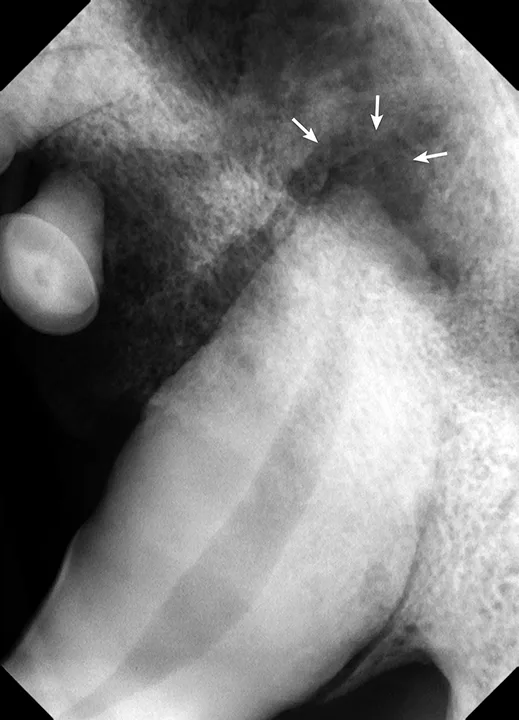

right maxillary fourth premolar of a dog showing inflammation and a root fragment extending into the oral cavity

Intraoral image of the right maxillary fourth premolar showing inflammation and a root fragment extending into the oral cavity (arrow)

After several months, the oral wound had not healed appropriately, and the patient demonstrated apparent continued discomfort, especially while eating. He was referred to a specialist for further treatment. Oral examination on referral revealed that the extraction site of the right maxillary fourth premolar was unhealed, with a root fragment extending from the inflamed gingiva (Figure 1).